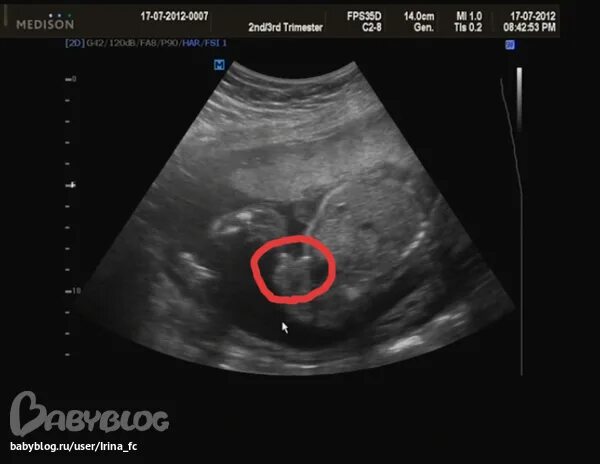

Пол 17 запись